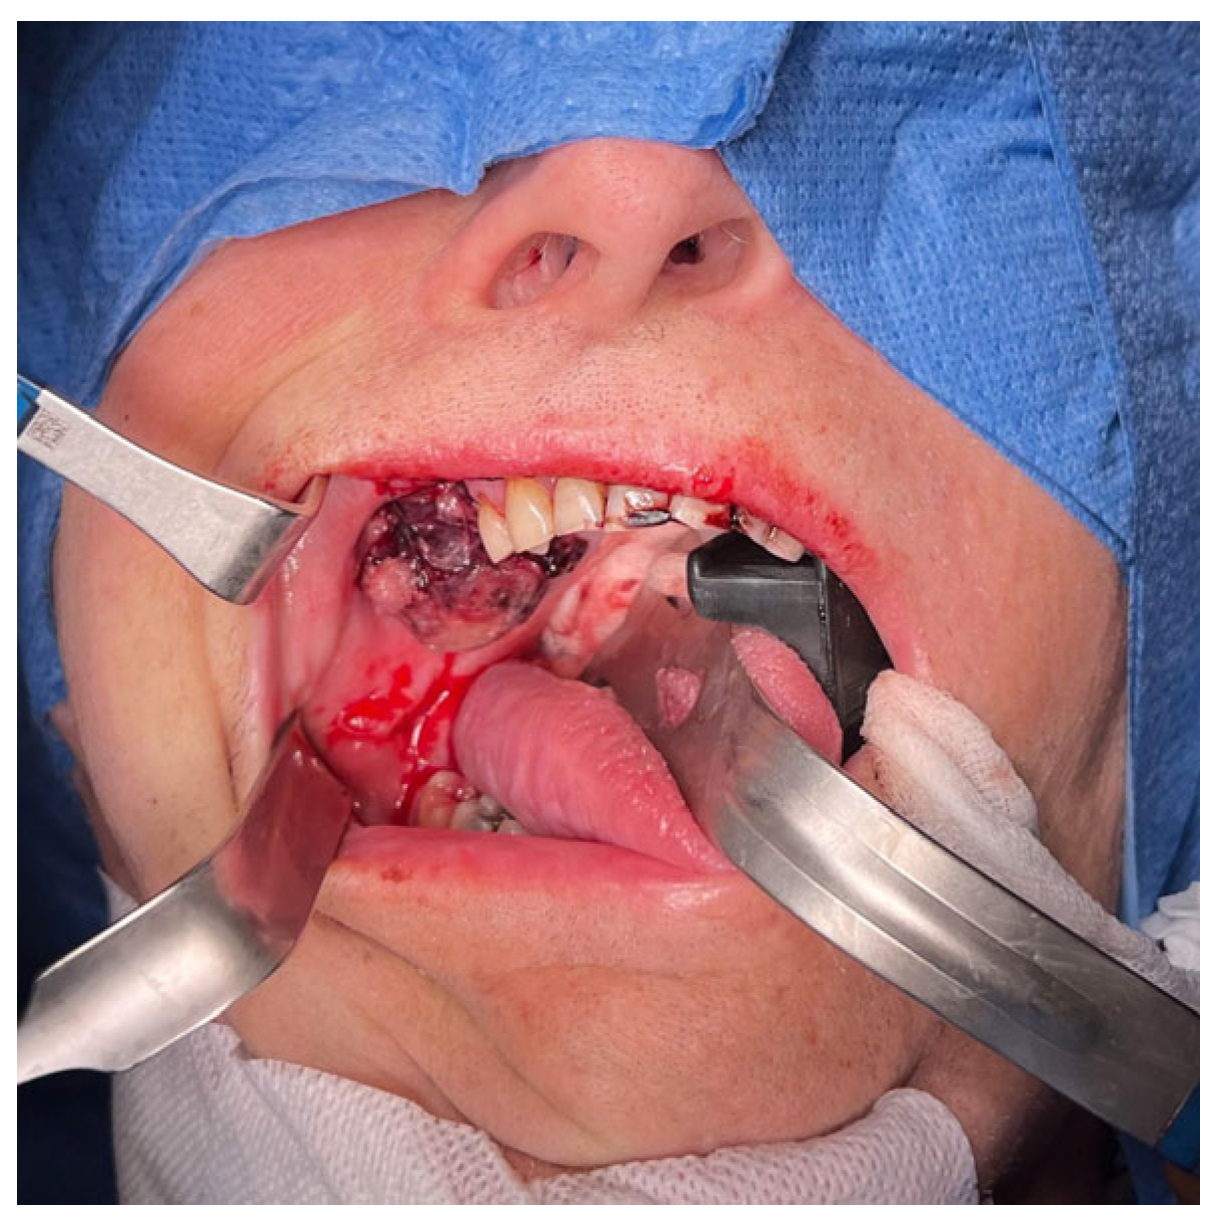

However, the patient’s overall condition deteriorated due to liver failure, resulting in severe bleeding from the lesion a few days after the incisional biopsy. Blood tests showed a drop in hemoglobin to 8.0 g/dL, a decrease in hematocrit to 24%, a reduction in erythrocyte count to 2.68 × 106 cells/µL, a decrease in platelet count to 95 × 103/µL, and an RDW-CV of 14.8%. To manage his escalating breathing difficulties and the risk of upper airway obstruction, as well as to prevent complications from bleeding, several procedures were performed. These included ligations of the ipsilateral external carotid artery, tracheotomy, percutaneous endoscopic gastrostomy (PEG), and red blood cell transfusions. Intraoperatively, bleeding from the entire surface of the tumor with necrotic–hemorrhagic changes was identified. The tumor was easily removed through curettage due to the fragility of its structure, leaving pseudo-capsule remnants (Figure 3). The residual masses were removed via functional endoscopic sinus surgery (FESS), with preservation of the floor of the right orbit. Within the cavity, individual spots with active bleeding were identified and coagulated. The medial wall of the maxilla was removed, creating a broad connection with the nasal cavity. The oroantral fistula was closed in two layers using Bichat’s fat pad and a trapezoidal mucoperiosteal flap. The material was sent for mycological, bacteriological, and histological examination.

Figure 1. Appearance of the tumor within the oral cavity at the level of teeth 14–18. Hemorrhagic changes in the tumor were visible after initial electrocautery.